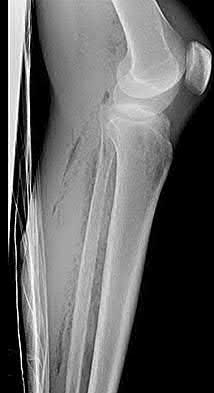

Question 3:

A 15-year-old boy presents with a permeative lytic lesion in the femoral diaphysis with aggressive periosteal reaction ('onion skinning'). Biopsy reveals uniform small round blue cells. Cytogenetic analysis of this tumor will most likely demonstrate which of the following translocations?

Correct Answer: t(11;22)

Explanation:

The clinical and radiographic description is classic for Ewing sarcoma. The characteristic cytogenetic abnormality is a balanced translocation t(11;22)(q24;q12), which fuses the EWS gene on chromosome 22 with the FLI1 gene on chromosome 11. This is seen in approximately 85-90% of Ewing sarcomas. t(9;22) is the Philadelphia chromosome (CML), t(X;18) is seen in synovial sarcoma, t(2;13) in alveolar rhabdomyosarcoma, and t(12;16) in myxoid liposarcoma.